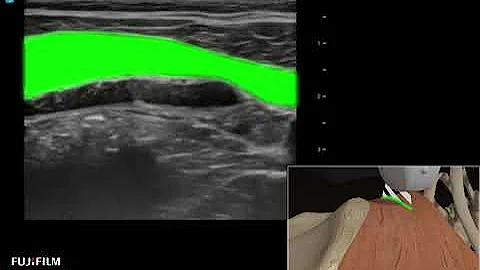

In this video we discuss the anterior approach to the quadratus lumborum block (also known as QL3, or the transmuscular